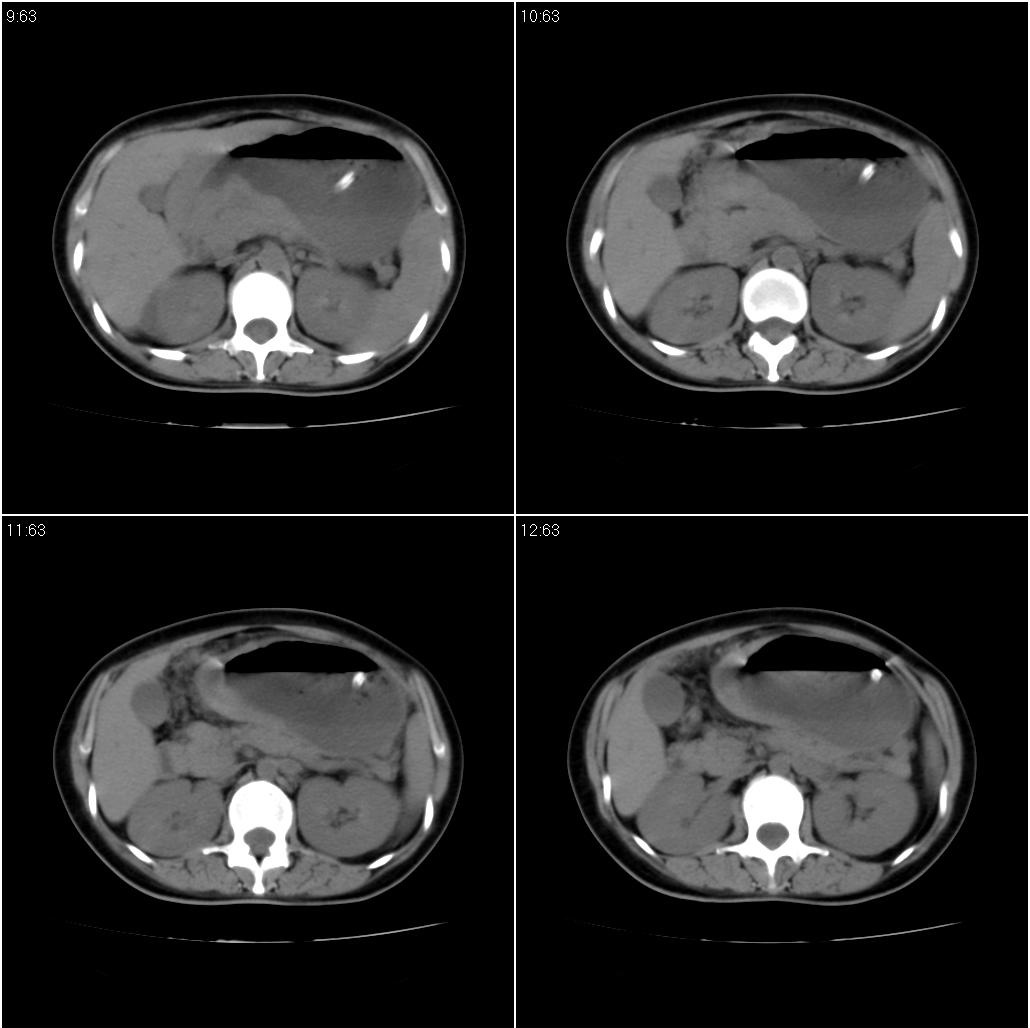

女性,33岁。4个月前因妊娠发现盆腔肿物。ca-125: 1100

胃幽门部癌伴小弯侧和腹腔淋巴结转移,胃内有胃管。

胃窦贲门胃小弯好像都厚啊 ,胃窦处比较明显,而且胃腔扩张明显,考虑胃癌伴梗阻。

胃壁局限性增厚,支持肿瘤性病变伴周围脓肿形成可能

未见明显肿大淋巴结,另肝脾大

支持;胃癌【浸润】幽门梗阻.胰头、胆囊及肝左叶受侵,副脾.

考虑胃窦占位并肝门部淋巴结转移

考虑胃窦部胃癌伴小弯侧和腹腔淋巴结转移。